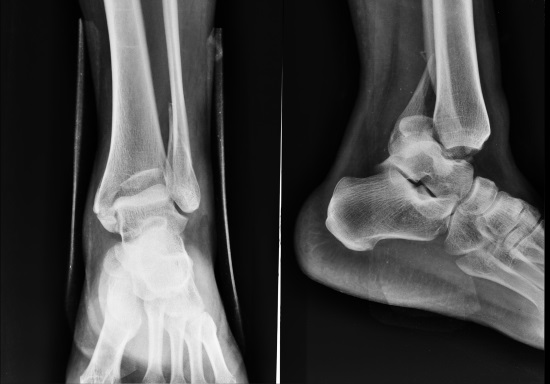

Диагноз ставят по клиническим симптомам, а подтверждают с помощью рентгенологического обследования. Лечение заключается во вправлении подвывиха, а при необходимости ‒ кратковременной иммобилизации (обездвиживании) сустава.

Из инструментальных методов исследования в диагностике подвывиха голеностопного сустава привлекаются:

- рентгенологическое обследование ‒ рентгенологические снимки делают в прямой и боковой проекциях (иногда ‒ в косой при необходимости проведения дифференциальной диагностики подвывиха голеностопного сустава с другими типами его повреждений). С помощью рентгенологических снимков оценивают степень смещения суставных поверхностей костей;

- магнитно‐резонансная томография (МРТ) ‒ ее проведение может понадобиться для оценки состояния мягких тканей, пострадавших при подвывихе. Также с помощью метода выявляются нарушения, характерные для патологий, которые спровоцировали слабость связок ‒ дегенеративно‐дистрофические, воспалительные и другие. Компьютерные срезы позволяют оценить характеристики глубоких слоев тканей.